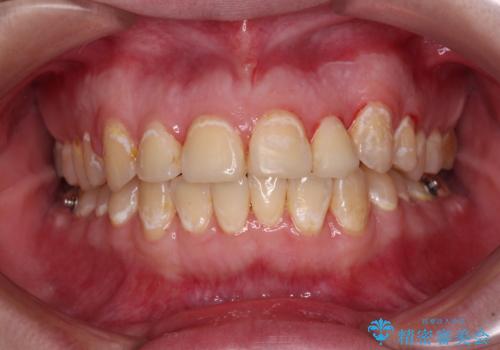

- 前歯のデコボコとクロスバイトが気になり、インビザラインによる矯正治療を希望して来院された患者様です。

上顎側切歯(上の真ん中から2番目の歯)が舌側転位している場合、無理して動かそうとすると歯髄壊死を起こすリスクが高い印象があります。

インビザライン単体でも治療は可能ですが、安全策としてインビザラインで歯列を移動する前に上顎前歯をワイヤー矯正で整え、その後上下歯列をインビザラインにて矯正治療を行うこととしました。